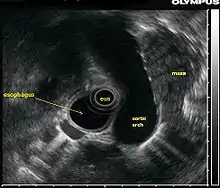

Эндосонография (эндоскопический ультразвук) — комбинированное исследование, при котором ультразвуковой датчик с помощью эндоскопа вводится в полость пищевода, желудка или кишечника с целью получить более чёткие изображения глубоко расположенных органов.[1] Может сочетаться с допплерографией для оценки кровотока в сосудах, а также с тонкоигольной аспирационной биопсией[2].

Благодаря высокой частоте (5—20 МГц) ультразвука повышается разрешающая способность исследования, что позволяет различить структуры стенки кишки и прилегающих органов на расстоянии 4—6 см, а также патологические образования малых размеров[1].